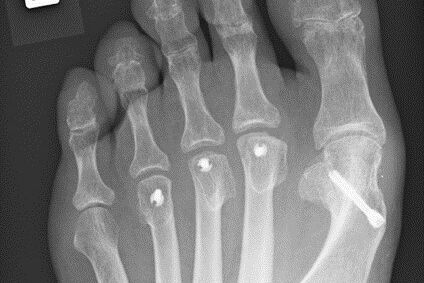

Therapie: distale Umstellung am MT1, Osteotomie an MT 2-4

Die operative Korrektur, bei der Umstellungsosteotomien an den Mittelfußknochen 1-4 links durchgeführt wurden, erfolgte im Mai 2018.

Bei anhaltenden Beschwerden wurde im Mai 2019 eine Röntgenaufnahme durchgeführt, die einen Schraubenüberstand von 1mm am Köpfchen des MT3 ergab. Dieser Befund wurde durch eine CT Untersuchung, bei der zusätzlich eine Arthrose im Grundgelenk der Großzehe und der zweiten Zehe gefunden wurde,  bestätigt.

Röntgenuntersuchungen